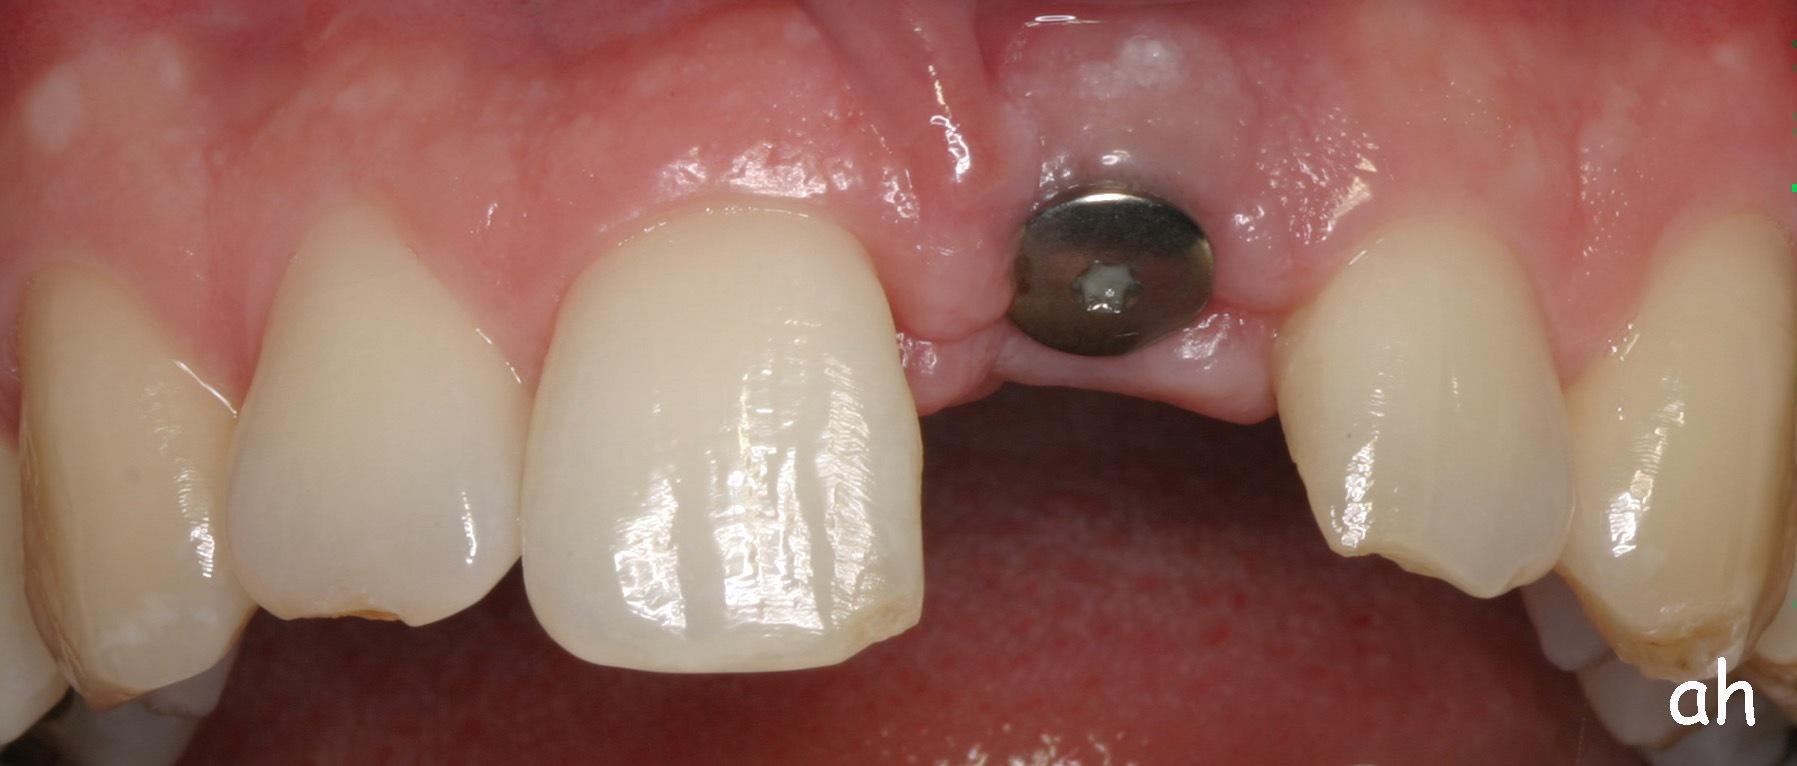

Exemple 3: Un implant à la place d'une incisive latérale supérieure droite. Sur cette image on voit le moignon en titane qui est vissé sur l'implant.

Exemple 3: Puis sur ce moignon, la couronne en céramique est scellée.

Exemple3: La couronne en place.